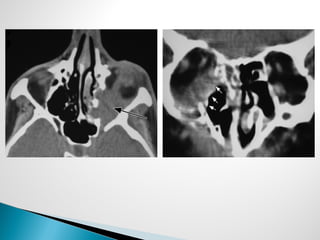

 Radiographic studies

◦ CT sinus

◦ MRI to assess tissue invasion, and orbital, intracranial, or

neural involvement

◦ Findings

 CT

 Bone erosion and extrasinus extension – classic finding

 Severe, unilateral mucosal thickening

 Thickening of periantral fat planes

 Radiographic studies ◦CT sinus ◦ MRI to assess tissue invasion, and orbital, intracranial, or neural involvement ◦ Findings  CT  Bone erosion and extrasinus extension – classic finding  Severe, unilateral mucosal thickening  Thickening of periantral fat planes

• #7 Nonseptated hyphae with branching at 90

• #35 CT scans; Left image: Destruction of medial wall of orbit with extension of disease into the orbit. Right image: Destruction of medial and inferior walls of the orbit with extension of disease into the orbit

• #36 Axial CT scans. Left image: invasion through lateral wall of the sphenoid sinus and into the cavernous sinus. Right image: lack of enhancement of the cavernous sinus due to fungal thrombosis